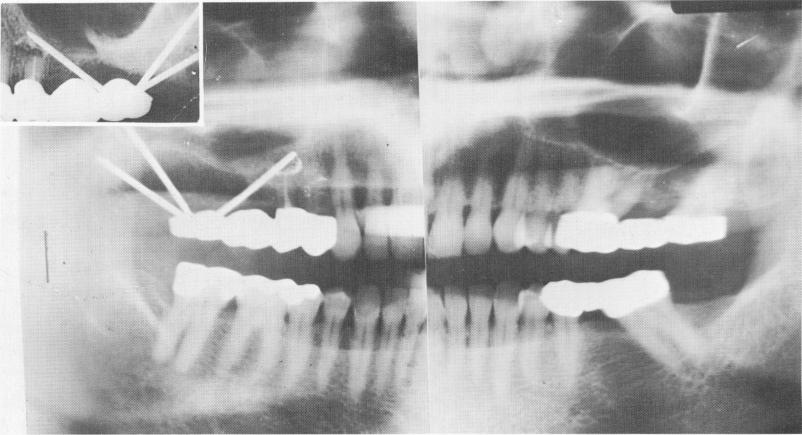

Fig. 15-67. A Panorex and intraoral radiograph showing the completed case. (From Linkow, L. I.: Atypical implantations for anatomically contraindicated situations, Dent. Concepts, Fall, 1967.)

3 Panorex and intraoral xray after upper endosseous pin implantation